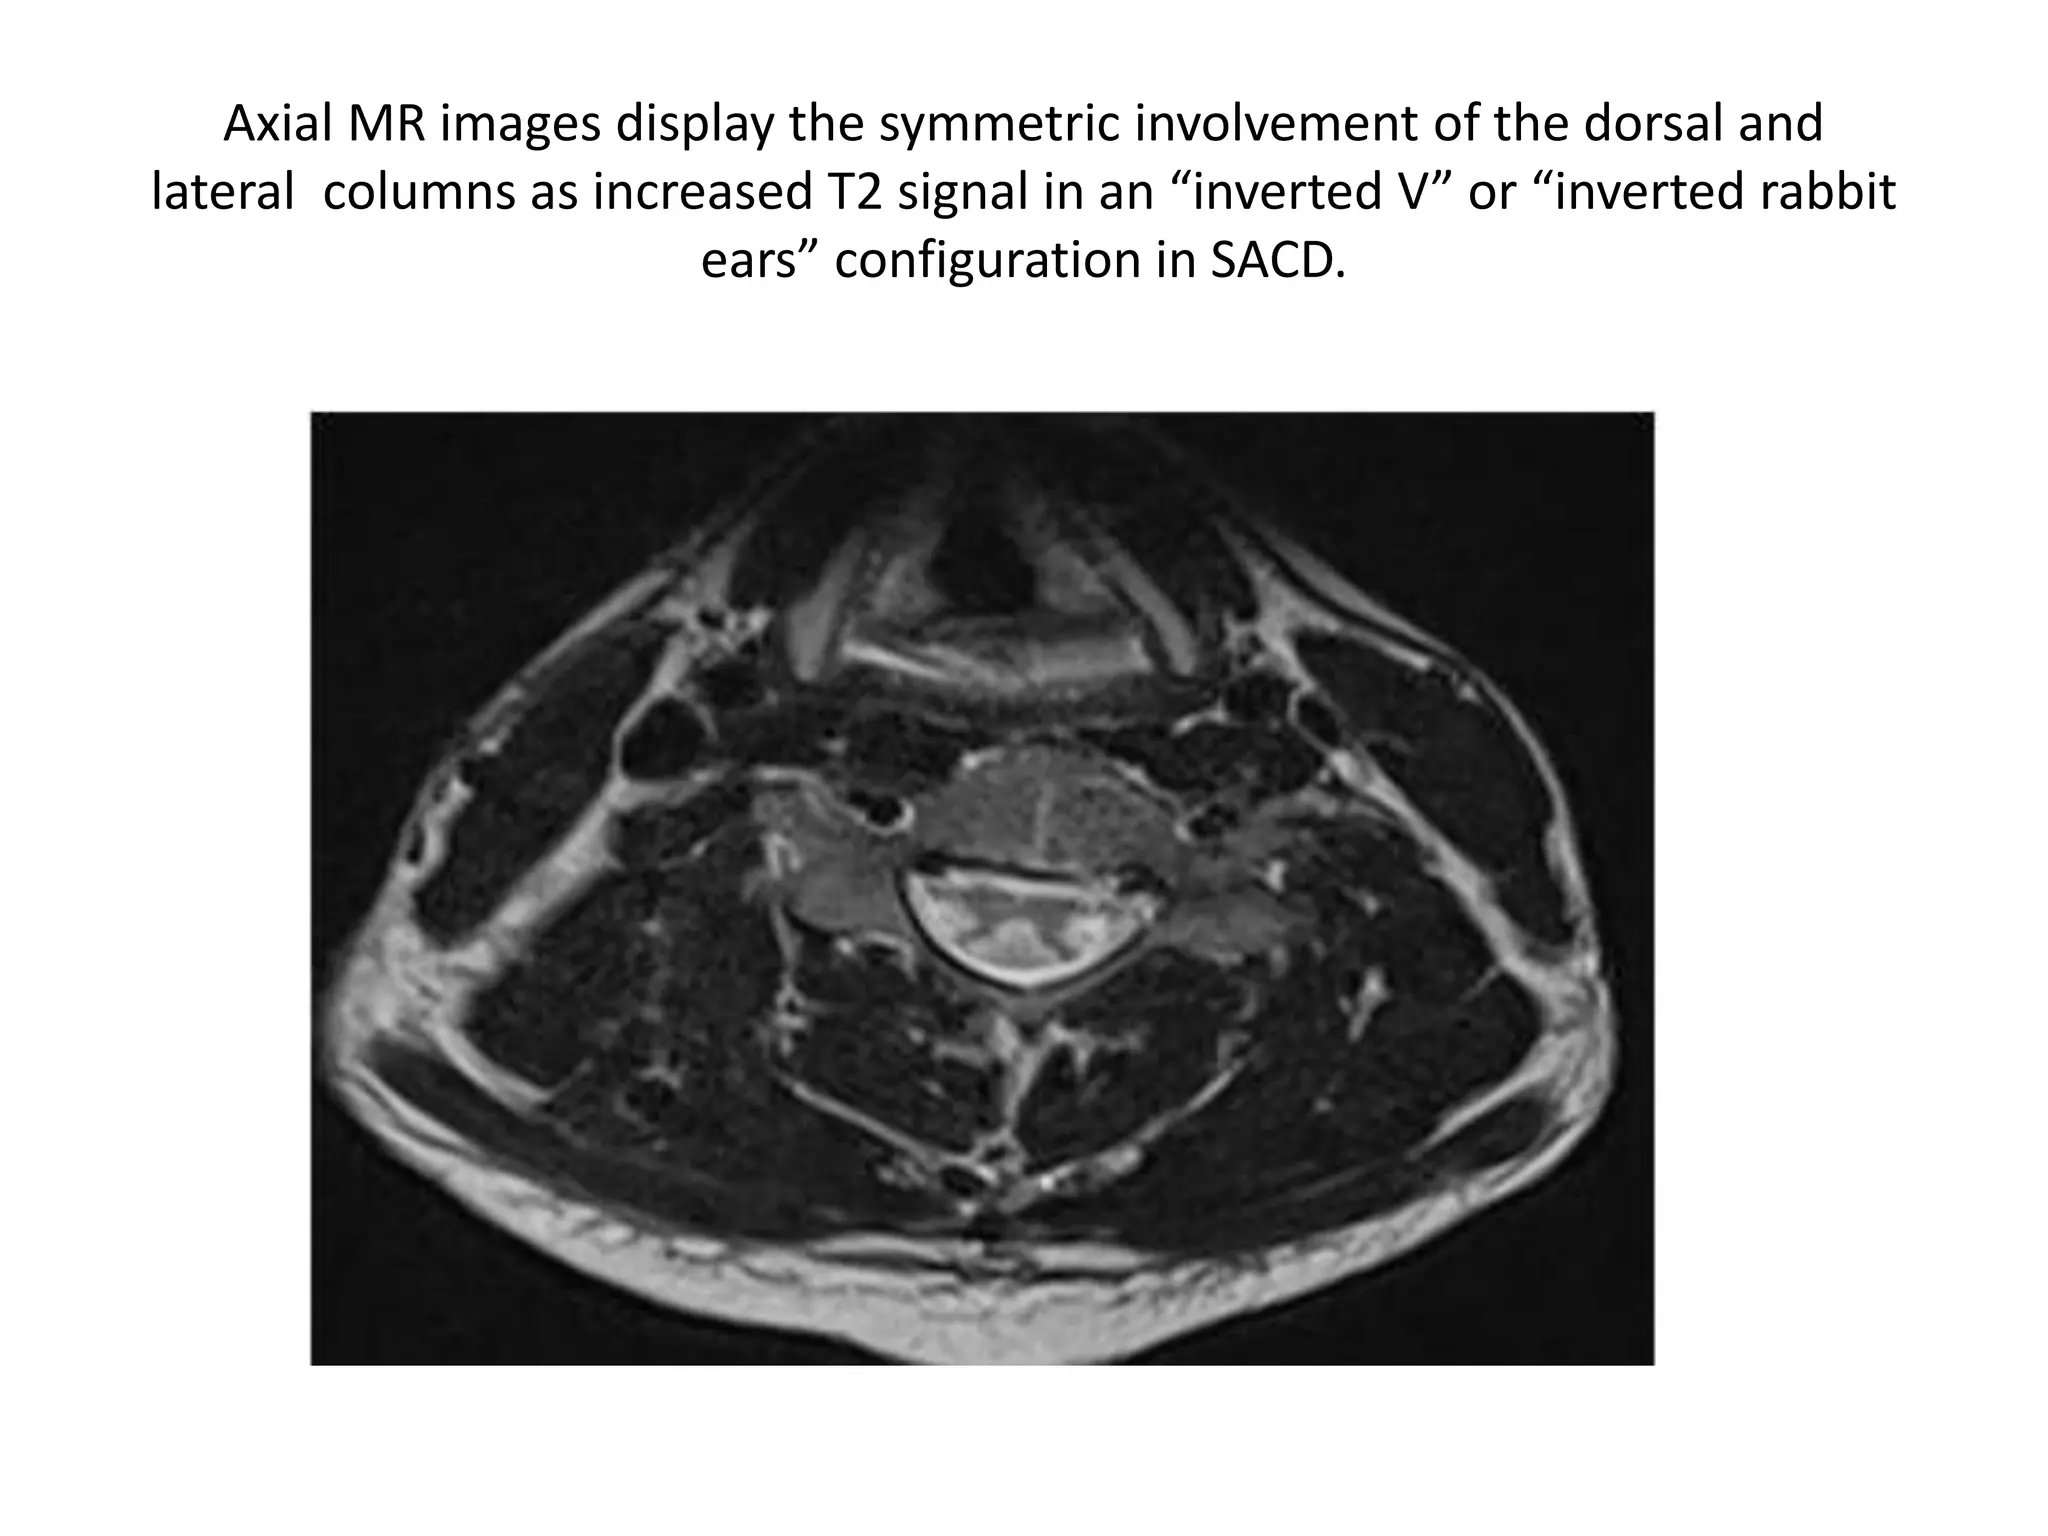

Axial MR images display the symmetric involvement of the dorsal and

lateral columns as increased T2 signal in an “inverted V” or “inverted rabbit

ears” configuration in SACD.